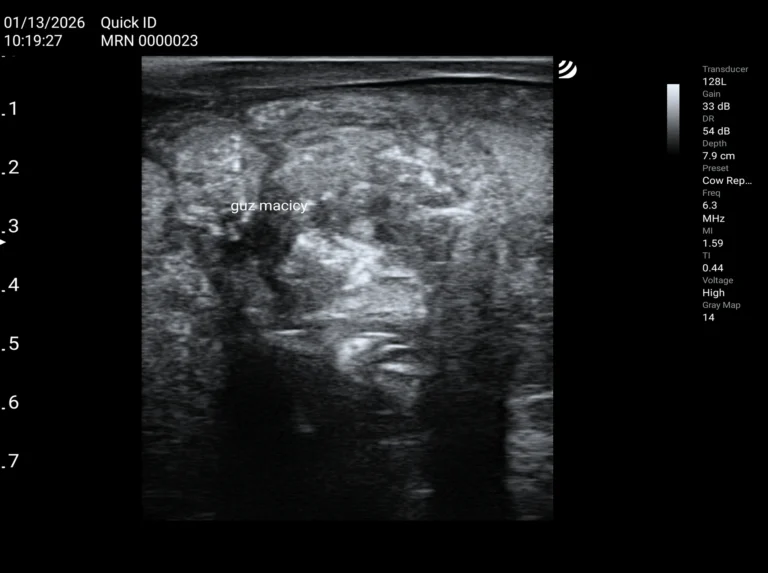

Przenośne ultrasonografy weterynaryjne

do kompleksowej diagnostyki małych

i dużych zwierząt.